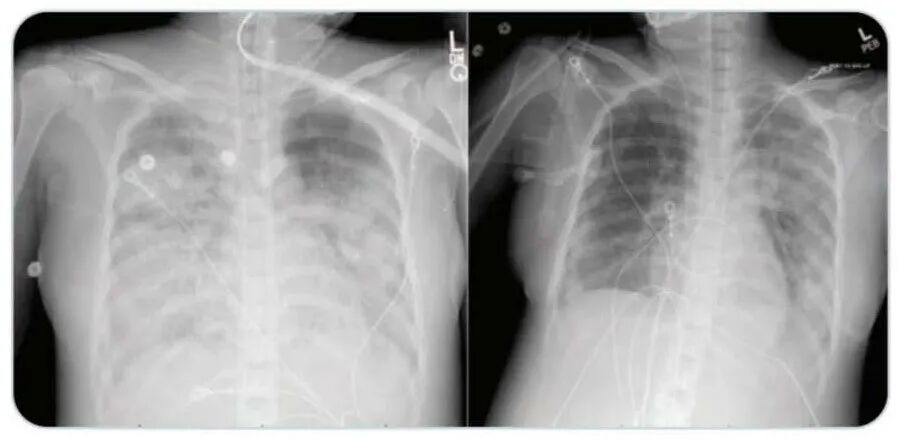

该患者本来是40多岁的健康女性,因呼吸道感染而入院,胸部CT影像显示为获得性肺炎。医院立即将其进行隔离以防止感染传播。入院24小时内,她的呼吸状况恶化。医院给她插管,并给予抗生素,包括利奈唑胺,哌拉西林-他唑巴坦和阿奇霉素治疗。

该患者在接受瑞德西韦(Remdesivir)治疗后,患者病情好转,需要的呼吸机支持明显减少,血氧水平和胸部CT检查结果好转。在入院治疗十四天后,已经可以撤离机械通气。目前患者已出院,正在在家中康复。